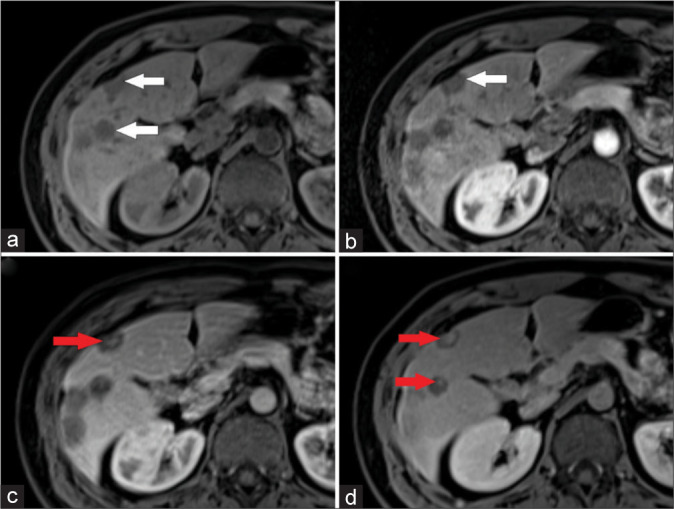

This study aims to provide a comprehensive understanding of primary hepatic angiosarcoma, a rare and aggressive malignancy, focusing on its diagnostic challenges and unique imaging characteristics. The objective is to delineate the distinctive features of angiosarcoma through computed tomography and magnetic resonance imaging modalities, contributing to improved diagnostic precision and adding valuable insights to the scientific literature. We present the case of a 25-year-old male with primary hepatic angiosarcoma, emphasizing the challenges in distinguishing it from other vascular tumors.